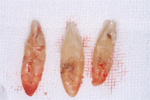

下顎前歯部も同様に抜歯を診断、抜歯後再生療法を実施しました。

骨の吸収が著しい下顎前歯部の3本

骨の吸収が著しい下顎前歯部の3本

骨の吸収が著しい下顎前歯部の3本